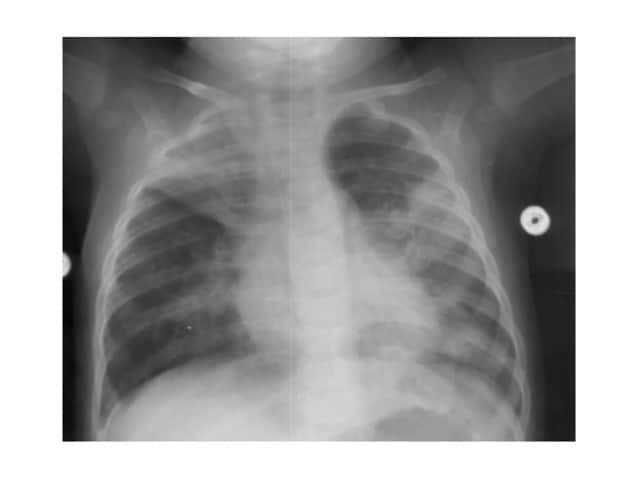

NEUMONÍA

Neumonia Neonatal Amzl 2013 19 638 (image/jpeg)